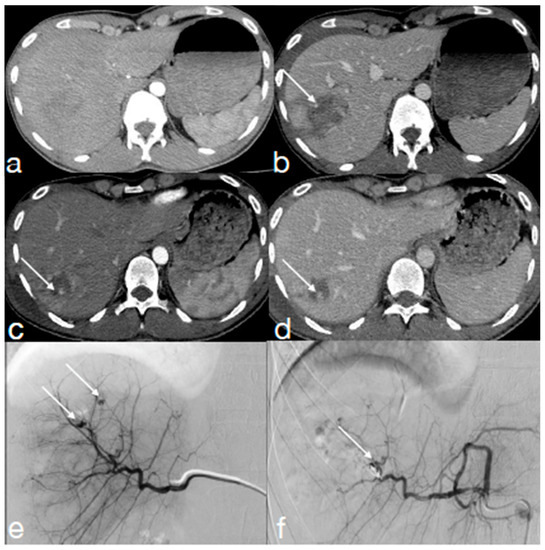

- Iacobellis, F.; Iacobellis, F.; Scaglione, M.; Scaglione, M.; Brillantino, A.; Brillantino, A.; Scuderi, M.G.; Scuderi, M.G.; Giurazza, F.; Giurazza, F.; et al. The additional value of the arterial phase in the CT assessment of liver vascular injuries after high-energy blunt trauma. Emerg. Radiol. 2019, 26, 647–654. [Google Scholar] [CrossRef]